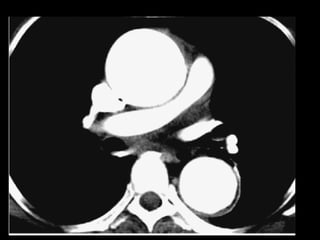

Dissecção aórtica

Tratamento:

Stanford A: cirúrgico

O acometimento da aorta ascendente ocorre em

50-75% das dissecções;

Complicações fatais relacionados à extensão da

dissecção às coronárias, valva aórtica, pericárdio ou

pleura;

Artefatos de movimento na raiz da aorta;

Fase adicional curta com gating cardíaco.

Multidetector CT of Aortic Dissection: A Pictorial Review 1. Radiographics march-april, 2010.